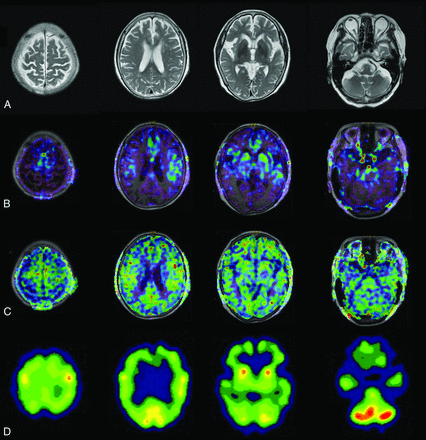

Case 1 was an 86-year-old woman with AD. Her MMSE score was 14. The ASL-MR imaging and SPECT images for this patient are shown in Fig 3. Case 2 was an 83-year-old woman with AD. Her MMSE score was 19. The images for this patient are shown in Fig 4. Case 3 was a 73-year-old woman with MCI due to AD. Her MMSE score was 23. The images for this patient are shown in Fig 5.

An 83-year-old woman with AD. The patient had an MMSE score of 19. Axial images of T2-weighted MR imaging (A), fused T1-weighted and PLD1.5 ASL-MR imaging (B), fused T1-weighted and PLD2.5 ASL-MR imaging (C), and brain perfusion SPECT (D). Both raters indicated a score of 4 for PLD1.5 and 2 (undetermined) for PLD2.5. One rater indicated a score of 3 (probably AD) and another rater indicated a score of 4 for SPECT.

A 73-year-old woman with MCI. The patient had an MMSE score of 23. Axial images of T2-weighted MR imaging (A), fused T1-weighted and PLD1.5 ASL-MR imaging (B), fused T1-weighted and PLD2.5 ASL-MR imaging (C), and brain perfusion SPECT (D). Both raters scored 4 for PLD1.5. However, 1 rater indicated a score of 1 (probably not AD) for PLD2.5 and 2 for SPECT, while another rater indicated a score of 0 (definitely not AD) for PLD2.5, and 1 for SPECT.